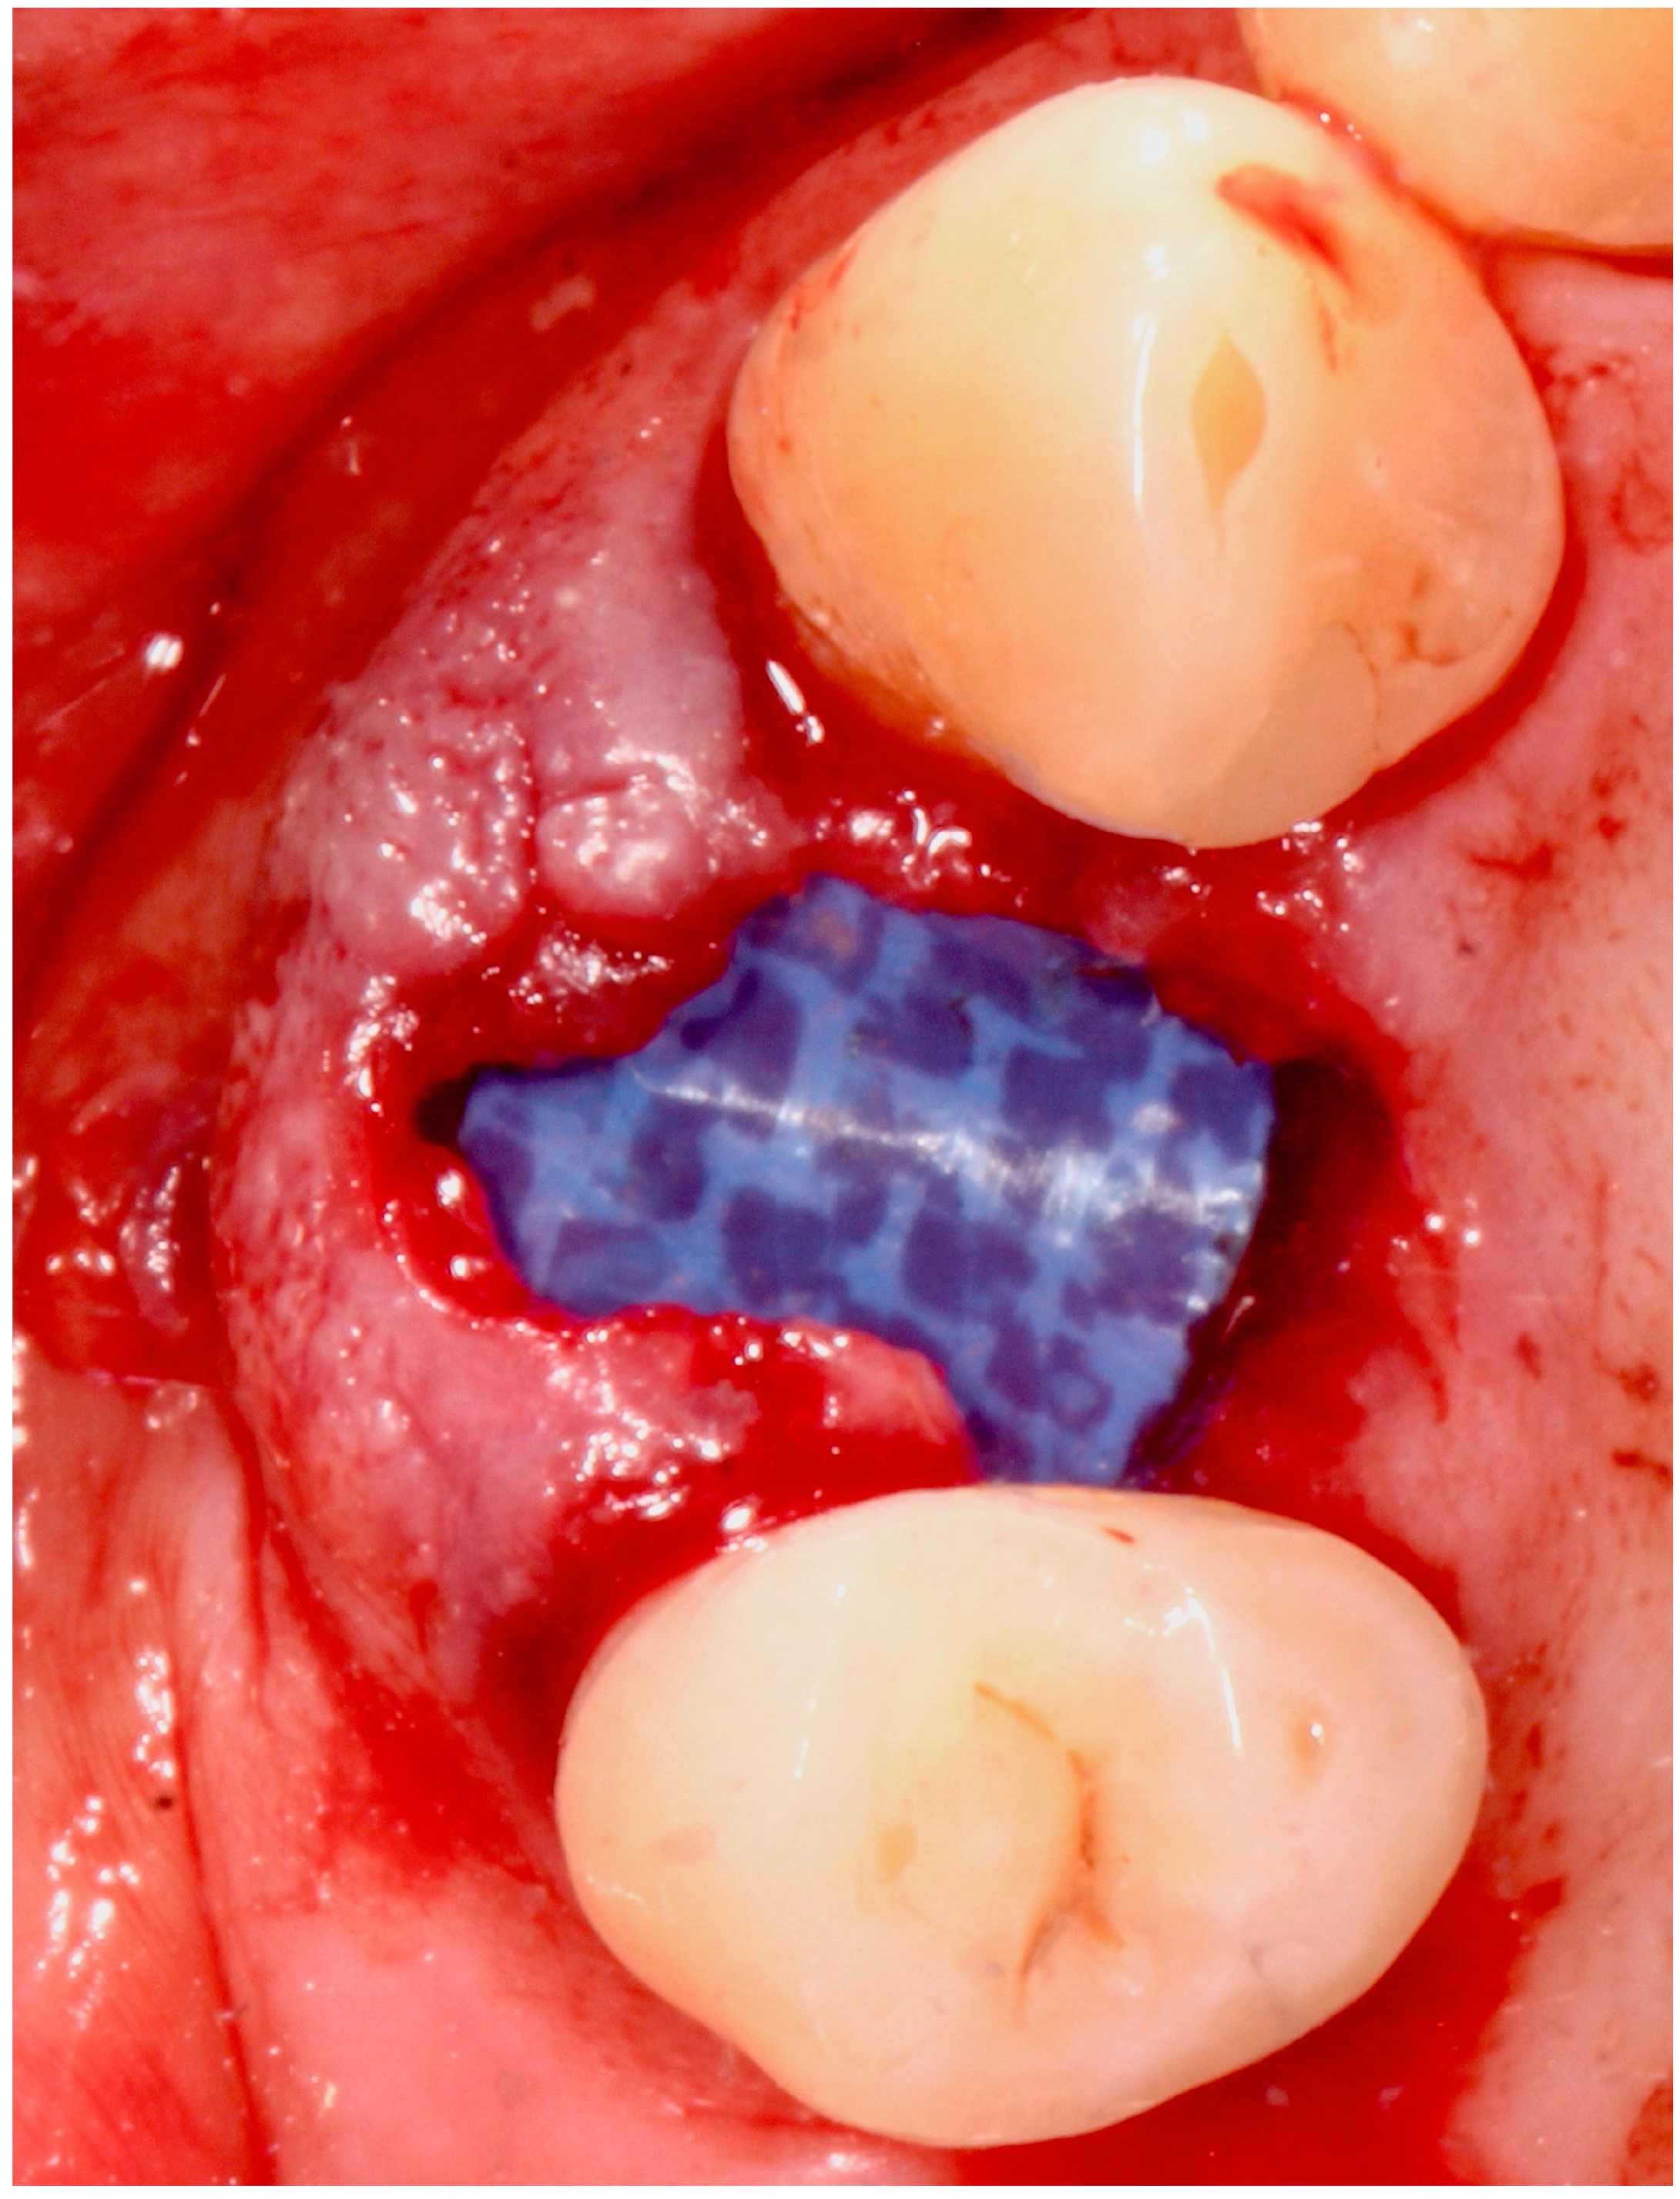

5.4. Surgical Technique